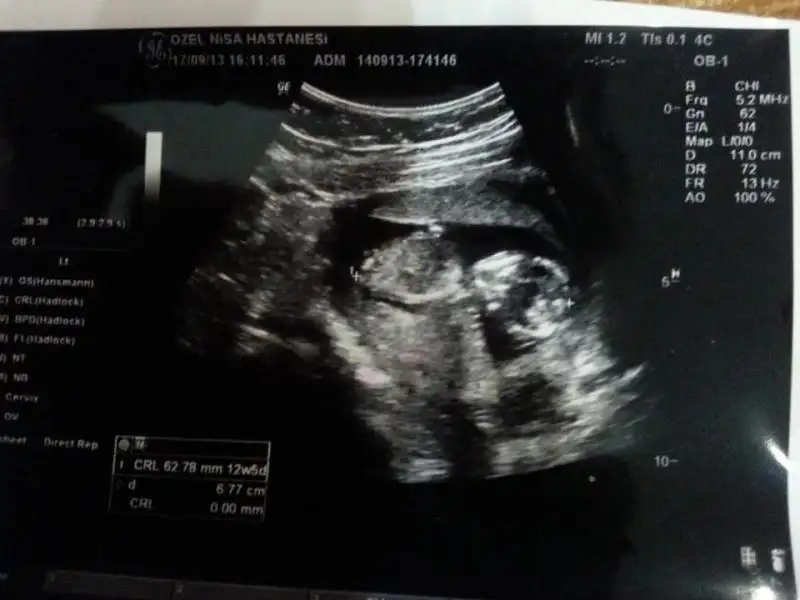

gurbet güzeli cnm bunlar en son fotolar 14+4 haftalık görüntüler...dr.10 gün öncesi kesin olmamakla beraber kıza benziyo demişti, bu hafta erkek dedi.bi bakarmısınız arkadaşlar sizce de erkek mi yoksa tekrar değişebilir mi?kafam cok karıstı..Eki Görüntüle 808673 Eki Görüntüle 808667

erkek cnm

Canım ben erkek diyorum pipi